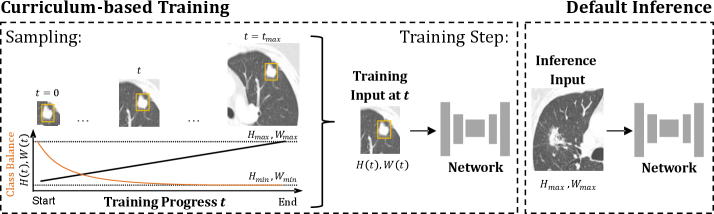

Refer to caption

Figure 1: Overview of the proposed Progressive Growing of Patch Size curriculum, illustrated for lung cancer segmentation (cancer regions highlighted with yellow bounding boxes). Training begins with the minimal patch size (Hmin,WminH_{min},W_{min}) and progressively increases the patch dimensions stepwise until the final maximal patch size (Hmax,WmaxH_{max},W_{max}) is reached. Smaller patch sizes provide a higher ratio of foreground to background voxels, which decreases as the patch size grows. During inference, the maximum patch size is used to capture maximal global context. Figure is adapted from [26].

Patch size increments are applied in the smallest feasible steps, with each axis adjusted independently. By gradually increasing the patch size in minimal increments, transitions between training stages are smoothed, as the segmentation tasks at successive patch sizes remain closely related. This design provides the network with a structured sequence of progressively more challenging tasks. An overview of this curriculum is illustrated in Figure 1.